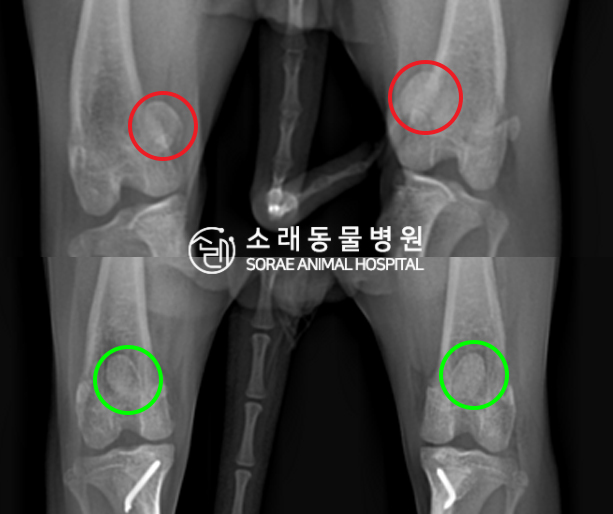

수술전과 수술후에 촬영한 도루의 슬개골

방사선 사진입니다. 나란히 놓고 비교해보니

슬개골의 위치에 확연한 차이가 있는 것을

확인해 볼 수 있는데요. 내측으로 탈구되어 있던

슬개골이 원래 제자리인 활차구에 예쁘게

자리 잡고 있는 모습을 확인할 수 있었습니다.